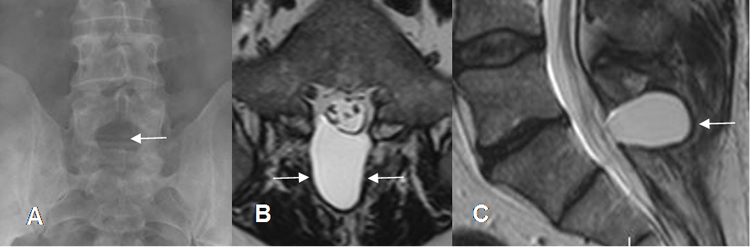

Fig 128. Seudomeningocele.

A: Rx AP. Ausencia de la apófisis espinosa de L5, por cambios Qx.

B: RM axial y C: RM sagital en T2. Por el defecto oseo amplio por donde protruye la duramadre y se forma colección de líquido cefaloraquideo, por seudomeningocele.